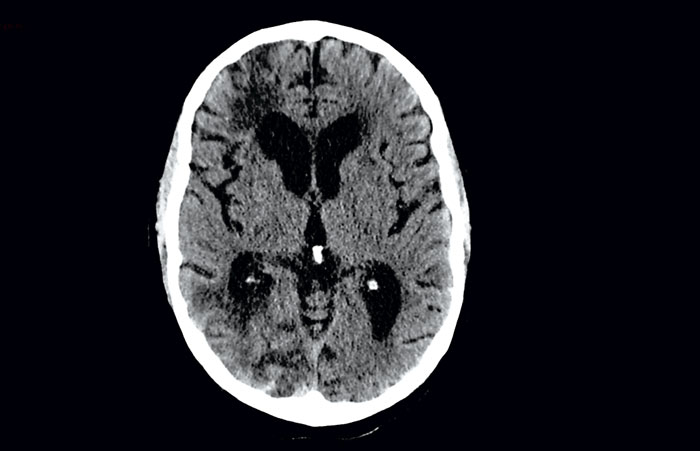

I frågan om huruvida antikoagulantia ska sättas in eller inte spelar åldern en viktig roll. Åldern påverkar risken för både stroke och blödning kontinuerligt, inte dikotomt vid 65 års ålder som i t ex HAS-BLED. Strokepatienterna är i genomsnitt betydligt äldre, 80 år, än de som ingått i de stora studierna av nya och äldre antikoagulantia (Figur 3). För närvarande finns blödningsdata från hela gruppen av hjärninfarkter, dvs även de som inte har förmaksflimmer. Dessa data visar att risken för blödning, i synnerhet intrakraniell och gastrointestinal, ökar mer efter 75 års ålder (Figur 4) [15]. Ökningen av blödningsrisken efter 75 års ålder kan vara relaterad till förekomst av småkärlssjuka. På DT syns småkärlssjuka som lakunära hjärninfarkter och förlust av vitsubstans (leukoaraios) (Figur 5). Med MRT kan man dessutom se mikroblödningar i hjärnparenkymet. Småkärlssjuka är även relaterad till större hjärnblödningar. En omfattande litteratur finns på området [16].

Svaret på frågan om ålderns betydelse blir att vi vet att risken för blödningar ökar med tilltagande ålder och att småkärlssjuka blir vanligare vid högre ålder. Däremot har vi inget svar på frågan om DT- eller MRT-fynd av småkärlssjuka ska vara kontraindikation för antikoagulationsbehandling av akut ischemisk stroke med förmaksflimmer.

Figur 5. 86-årig kvinna med förstagångsstroke och förmaksflimmer. DT-hjärna visade förekomst av småkärlssjuka med förlust av vitsubstans, leukoaraios (mörka områden bredvid sidoventriklarna).